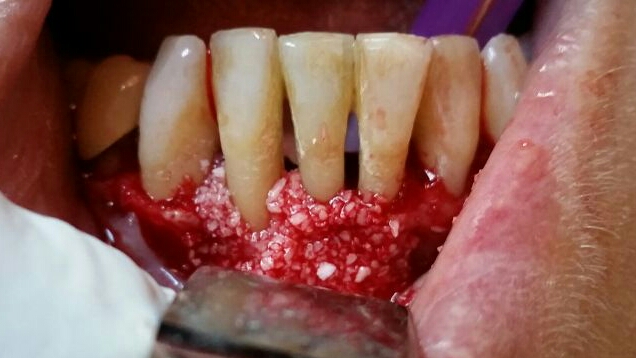

Chirurgie - Adiţie de os